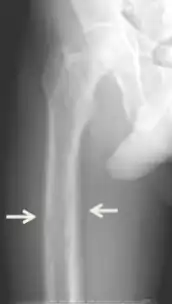

Los síntomas inespecíficos incluyen sensación de cansancio y sed, existen cambios de humor que incluyen, tristeza, debilidad y irritación junto con otros síntomas como el picor, dolor de cabeza, dolor articular, olvido y dolor abdominal.[8][4][9][1] Los síntomas más específicos relacionados con los niveles de calcio y fosfato elevados en sangre incluyen dolor de huesos (osteodinia) y sensibilidad ósea que son comunes y están relacionados con sensibilidad de músculo proximal. Otros signos pueden incluir pancreatitis, piedras de riñón, calcificaciones corneales, adelgazamiento de huesos largos y calcificaciones hipodérmicas que pueden ser palpables en algunos pacientes.[2]

Las afecciones debidas a pérdida de hueso como la osteopenia y la osteoporosis son comunes en el hiperparatiroidismo terciario junto con las fracturas patológicas. Las pseudoacropaquias de los dedos también puede ser indicativo de un hiperparatiroidismo terciario severo debido a una resorción ósea excesiva en las falanges distales.[8][1]

El diagnóstico incluye análisis tanto clínicas como de laboratorio. Las investigaciones radiológicas buscan signos de pérdida de hueso en manos y pelvis, rasgo característico hiperparatiroidismo terciario.[8] Otro examen clínico puede incluir la clasificación de la debilidad muscular, que se realiza pidiendo al paciente que se ponga de pie desde una posición sentada con las manos cruzadas sobre el pecho.[4] Los análisis de laboratorio incluyen determinación del nivel de calcio de sangre y de fosfatasa alcalina, los cuales están siempre aumentados en el hiperparatiroidismo terciario. Otros resultados comunes de laboratorio incluirían niveles disminuidos de vitamina D, hormona paratiroidea elevada de sangre elevada e hiperfosfatemia.[9][1]